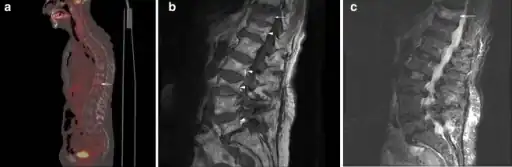

Example of vertebral compression fracture.

A potential complication of a vertebral compression fracture is avascular necrosis of the vertebral body, which is called Kümmel's disease, and may appear with the intravertebral vacuum cleft sign (at white arrow in image).[4]